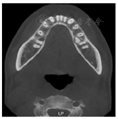

。CBCT示11牙根向远中明显弯曲,牙根发育至Nolla9期;21牙根发育至Nolla9期,腭侧见两颗正置锥形多生牙,牙根未发育完成;12、22牙根发育至Nolla9期;23牙冠近中倾斜至62根方。

CBCT示:上颌恒牙胚萌出间隙不足,根据Moyers混合牙列分析法,牙弓现有长度为177.4 mm,牙弓应用长度为181.6 mm,拥挤度为4.2 mm。42缺失;11、21、22发育至Nolla9期;55、16、65、46冠部低密度影及牙本质中层,根管内未见高密度充填影,根尖周未见明显异常。53、63牙根吸收不足1/3,13、23发育至Nolla8期。

2020年12月21日口腔颌面部CBCT精确定位、笑气镇静+4%肾上腺素-盐酸阿替卡因注射液局部浸润麻醉下先行拔出恒中切牙腭侧多生牙,同期切除部分牙龈暴露双侧上中切牙牙冠最宽径。4个月后11仍未有萌出迹象,21萌出,与31反

垫舌簧活动矫治器利用后牙区乳牙及已萌恒牙作为支抗对11进行橡皮链牵引,并在12、21及22舌侧增加舌簧。活动矫治器在上颌腭部增加螺旋扩弓器,对上颌骨进行慢速扩弓纠正其横向发育不良。因无确切证据表明上颌存在失状方向上发育不足,故暂不考虑佩戴上颌前方牵引器。11橡皮链牵引持续6个月,扩弓持续11个月,扩弓结束后保持3个月。